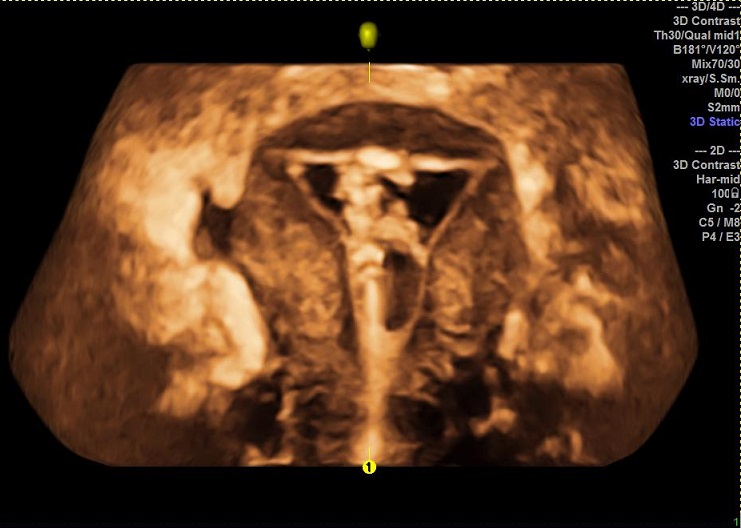

女性,27岁,原发性不孕2年。常规二维超声子宫及宫腔置管后水造影二维、三维均未发现明显异常。子宫输卵管实时三维超声造影显示:双侧输卵管走形柔顺自然,由宫角部延展而出,近端稍纤细,远端略粗大,造影剂从伞端溢出后环绕于卵巢周边,并可见盆腔内均匀弥散。诊断:双侧输卵管通畅